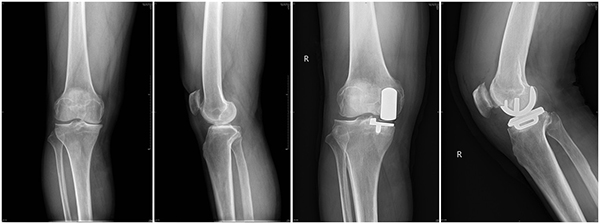

徐醫(yī)附院骨關(guān)節(jié)科成功開(kāi)展首例全生物型牛津單髁膝關(guān)節(jié)置換術(shù)

黃淮網(wǎng)  近日,在院領(lǐng)導(dǎo)的關(guān)心和支持下,在骨關(guān)節(jié)科、手術(shù)室的配合下,徐州醫(yī)科大學(xué)附屬醫(yī)院骨關(guān)節(jié)科盧文海、史思峰及孫少松醫(yī)師成功為一位膝關(guān)節(jié)骨性關(guān)節(jié)炎患者實(shí)施了全生物型牛津單髁膝關(guān)節(jié)置換術(shù)。該手術(shù)為膝關(guān)節(jié)單髁置換手術(shù)中的一種新的方式,為徐醫(yī)附院首次采用,為該院骨關(guān)節(jié)科在膝關(guān)節(jié)單髁置換技術(shù)方面又增加了一項(xiàng)新的內(nèi)容。

來(lái)自安徽宿州的患者王先生,因?yàn)橄リP(guān)節(jié)疼痛3余年、加重1年入院,診斷為“右膝關(guān)節(jié)骨性關(guān)節(jié)炎”,患者右側(cè)膝關(guān)節(jié)內(nèi)翻畸形,內(nèi)側(cè)間隙疼痛明顯,無(wú)法自主蹲起及長(zhǎng)距離行走。經(jīng)骨關(guān)節(jié)科醫(yī)師討論認(rèn)為:患者病痛位于膝關(guān)節(jié)內(nèi)側(cè),內(nèi)側(cè)間室的軟骨破壞明顯,具備內(nèi)側(cè)單髁置換手術(shù)指征,無(wú)手術(shù)禁忌癥,于2021年7月15日在盧文海副主任醫(yī)師、史思峰副主任醫(yī)師、孫少松主治醫(yī)師協(xié)作配合下進(jìn)行了右膝關(guān)節(jié)內(nèi)側(cè)全生物型單髁置換術(shù)。手術(shù)順利。術(shù)后第二天患者即可自行下地行走,術(shù)后功能恢復(fù)良好。7月20日,王先生出院。8月27日,他來(lái)院復(fù)查時(shí),自己行走自如,屈伸活動(dòng)良好。

盧文海副主任醫(yī)師介紹,膝關(guān)節(jié)單髁置換相對(duì)于全膝關(guān)節(jié)置換而言是一種微創(chuàng)術(shù)式。只對(duì)膝關(guān)節(jié)內(nèi)側(cè)或外側(cè)間室進(jìn)行表面置換,不需要去除膝關(guān)節(jié)內(nèi)的前后交叉韌帶,最大限度的保留了患者的本體感覺(jué)和關(guān)節(jié)功能,具有創(chuàng)傷小、疼痛輕、恢復(fù)快的優(yōu)點(diǎn)。而生物型牛津單髁膝關(guān)節(jié)置換術(shù)(Cementless Oxford Unicompartmental Knee Arthroplasty,COUKA)自2004 年由牛津大學(xué)首創(chuàng)以來(lái),國(guó)外臨床應(yīng)用較多,但在國(guó)內(nèi)起步較晚。使用生物型牛津單髁膝關(guān)節(jié)假體可避免骨水泥相關(guān)并發(fā)癥,縮短手術(shù)時(shí)間;減少透亮線(xiàn),以期望降低翻修率。不過(guò)生物型牛津單髁假體的使用要嚴(yán)格掌握適應(yīng)癥,對(duì)于骨質(zhì)疏松、局部骨壞死、術(shù)后活動(dòng)較大、髁畸形等患者要慎重選擇。